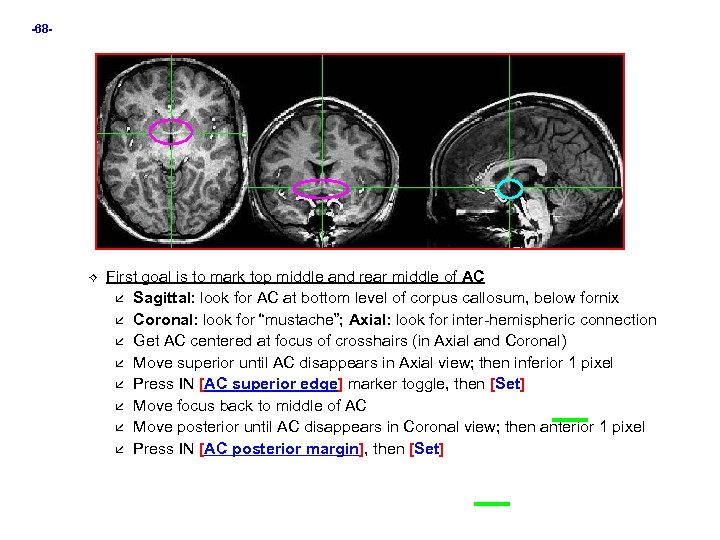

-68 - First goal is to mark top middle and rear middle of AC Sagittal: look for AC at bottom level of corpus callosum, below fornix Coronal: look for “mustache”; Axial: look for inter-hemispheric connection Get AC centered at focus of crosshairs (in Axial and Coronal) Move superior until AC disappears in Axial view; then inferior 1 pixel Press IN [AC superior edge] marker toggle, then [Set] Move focus back to middle of AC Move posterior until AC disappears in Coronal view; then anterior 1 pixel Press IN [AC posterior margin], then [Set]